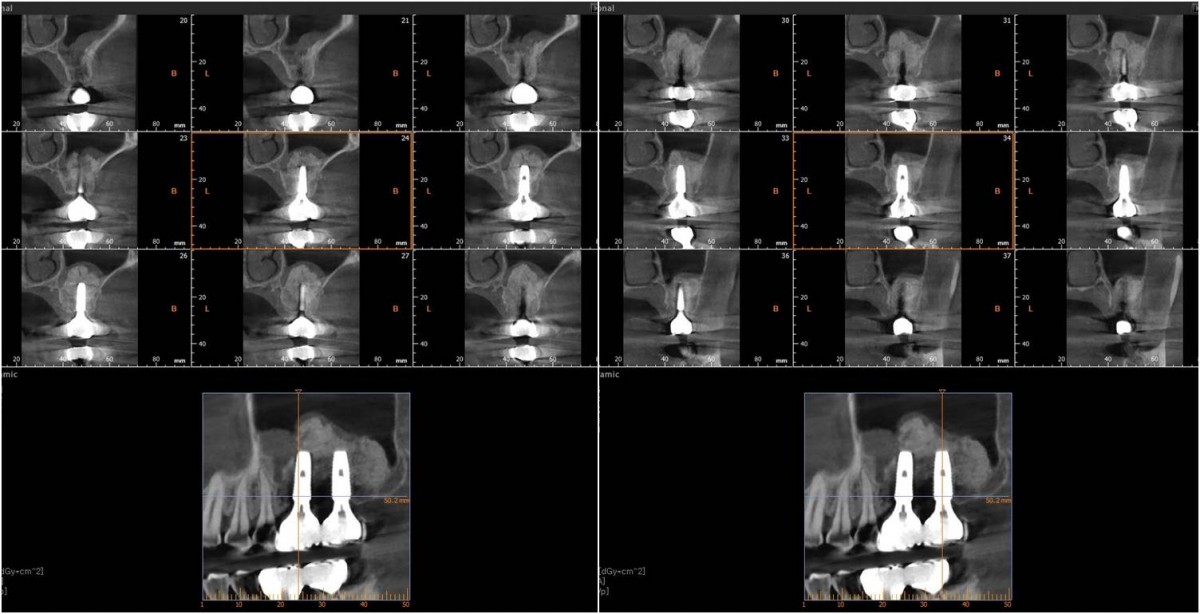

▲Panoramic radiograph before the implant surgery in the lower left area.

▲post-op panoramic radiograph.

▲. Panoramic radiograph after implant placement in the maxilla.(3 weeks after implant placement in the mandible)

▲Panoramic radiograph after 1 year of the crown delivery.